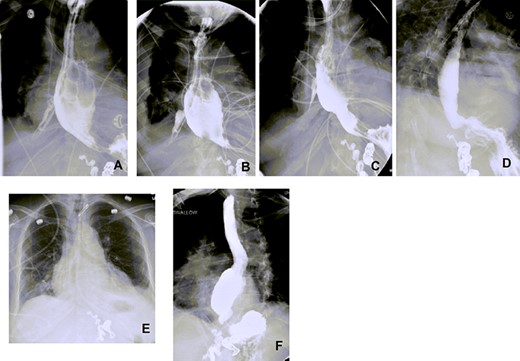

Three weeks postdischarge, she was re-admitted with fevers and shortness of breath and was found to be fluid overloaded. Esophagogram showed a large 2.5-cm defect in the mid-distal esophagus with extravasation of contrast material into right pleural cavity without communication to the bronchial tree (Fig. 1). An OGD further corroborated these findings. 16F Salem nasogastric tube was advanced into esophagus and placed into the bottom of the right pleural space.10F nasoduodenal feeding tube was also placed.

Chest x-ray (CXR), CT chest and esophagogram on the day of admission. (A) CXR showing right-sided pleural effusion and consolidation, (B) CT chest showing the empyema cavity and the fistula tract, (C) esophagogram showing a 2.5-cm mid-distal esophageal defect with contrast extravasting into the right pleural space.